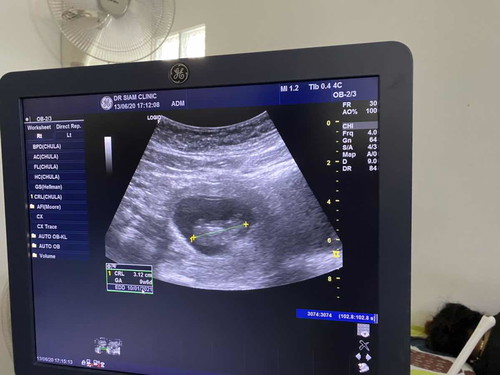

เป็ยภาวะแท้งคุกคามค่ะ ฉีดยากันแท้งมาตั้งแต่ 6 วีค ตอนนี้ 9วีค 6 วันแล้ว ไม่มีเลือดออกแล้ว หัวใจลูกเต้นดี ❤️ เหลือฉีดอีก 2 เข็ม ?